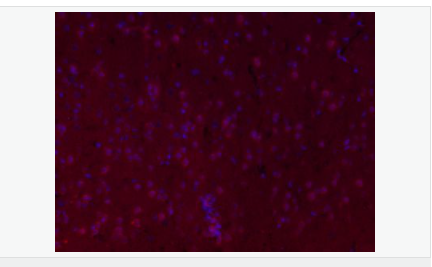

交叉反應:Mouse,Rat(predicted:Human,Pig) 推薦應用:IHC-P,IHC-F,IF,ELISA

| 產(chǎn)品應用 | ELISA=1:5000-10000 IHC-P=1:100-500 IHC-F=1:100-500 IF=1:100-500 (石蠟切片需做抗原修復) not yet tested in other applications. optimal dilutions/concentrations should be determined by the end user. |